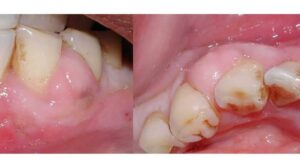

1. Tooth Decay (Cavities)

Cavities are one of the most common causes of tooth pain, especially when pressure is applied during chewing. As decay progresses, it weakens the outer enamel and exposes more sensitive inner layers of the tooth.

Cavities weaken the enamel and expose the inner layers of the tooth. When you chew, pressure hits these sensitive areas.

Signs:

- Sharp or localized pain

- Sensitivity to sweets or temperature

- Visible holes or discoloration

Treatment:

- Fillings (early stage)

- Crowns (advanced cases)